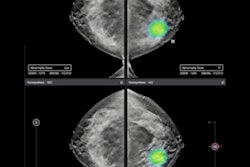

The pair of studies conducted by Dr. Fredrik Strand, PhD, from the Karolinska Institute and his research team featured performance results of Lunit Insight MMG, a commercial AI solution for breast cancer detection from mammograms.

The company said its algorithm showed the best accuracy in the JAMA Oncology study, based on 8,805 breast cancer cases, with sensitivity around 15 percentage points higher than the sensitivity of the other two algorithms. It's sensitivity also surpassed that of the first-reader radiologists, and it achieved a synergistic sensitivity of 88.6% in the combination of first readers and Lunit's AI algorithm.

In the Lancet Digital Health study, Lunit Insight MMG rarely missed any cancers in the majority of mammograms receiving a low abnormality score when assessing data with no radiologists involved. If no radiologist resources were used for 60% of women with the lowest AI scores and were invested in MRI for the top 2% of AI scores, a net 103 of 547 cancers would potentially have been detected up to two years earlier. This corresponds to a detection rate of 68 cancers per 1,000 supplemental screening examinations, according to the company.